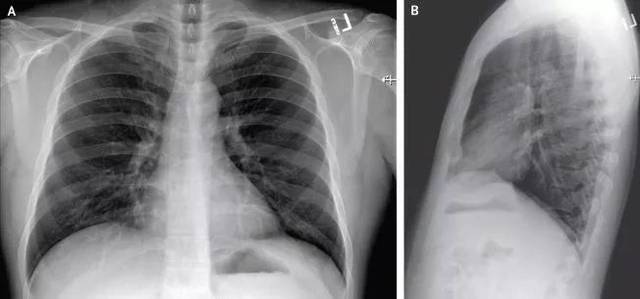

2020年1月19日,病患发病4天的后前胸和外侧胸片。(取自新英格医学杂志)

住院的第六天,这名患者的胸部X光片显示出肺炎的特征,并持续高烧,需要用氧气,且多个部位的样本出现新型冠状病毒的阳性结果,因此医生们决定让他使用尚未获批准的瑞德西韦;患者在次日就明显好转。